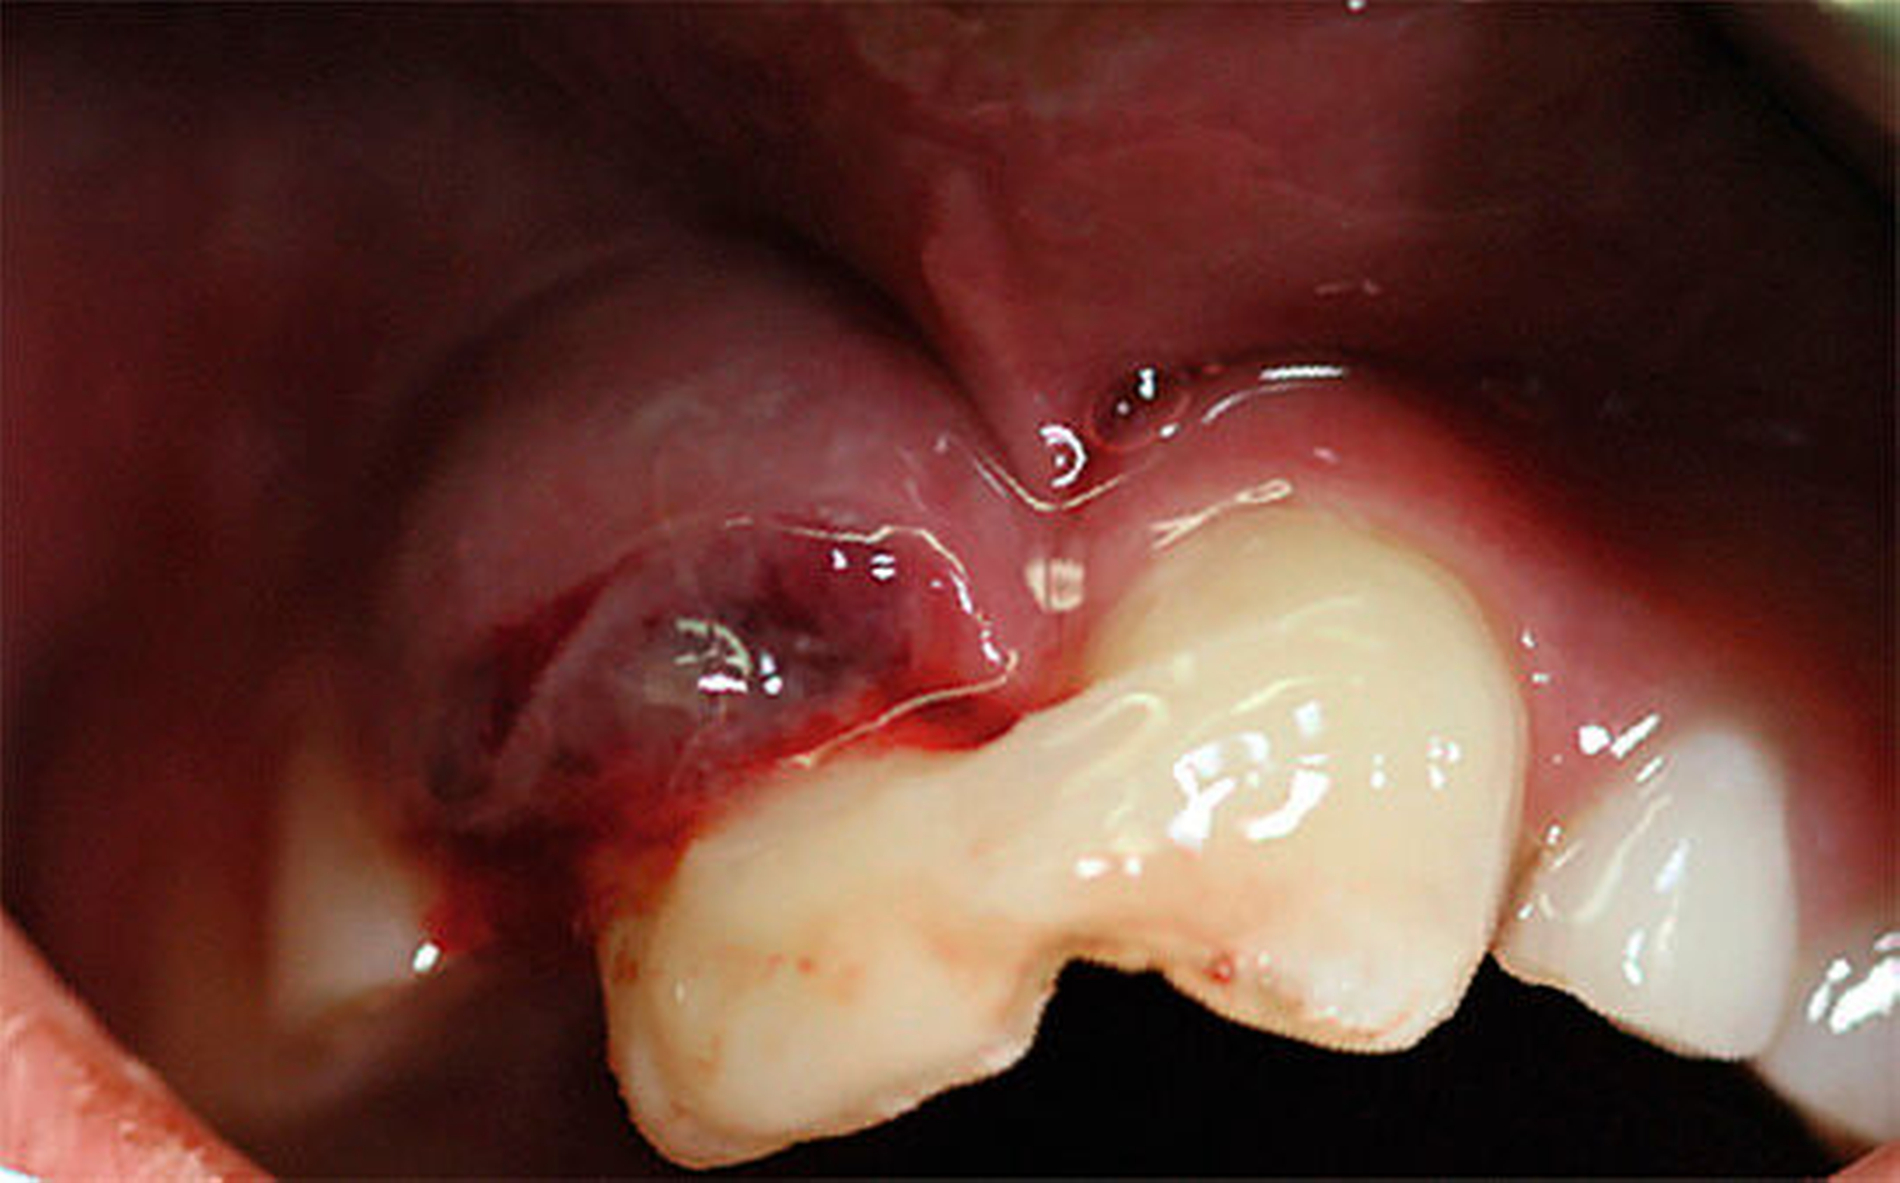

Eine neunjährige Patientin stellte sich mit einer seit vier Tagen bestehenden, progredient wachsenden, dunkelroten Schwellung im Vestibulum regio 11 in der Abteilung für Mund-, Kiefer- und plastische Gesichtschirurgie der Universität Rostock vor. Zahn 11 hatte sich anamnestisch im Verlauf der vergangenen 24 Stunden drittgradig gelockert und mit 3 bis 4 mm deutlich aus der Alveole gehoben. Daher war von einem niedergelassenen Zahnarzt bereits eine Kunststoffverblockung an Zahn 21 durchgeführt und die Patientin mit Bitte um operative Entlastung und postoperative Schienung überwiesen worden (Abbildung 1). Am Sulcus des Zahnes 11 fand sich eine eitrige Sekretion. Die klinische Untersuchung ergab des Weiteren einen erhöhten Lockerungsgrad an den Milchzähnen 52 und 53. Aus dem erweiterten Parodontalspalt von Zahn 11 entleerte sich unter Druck blutig tingiertes Sekret.